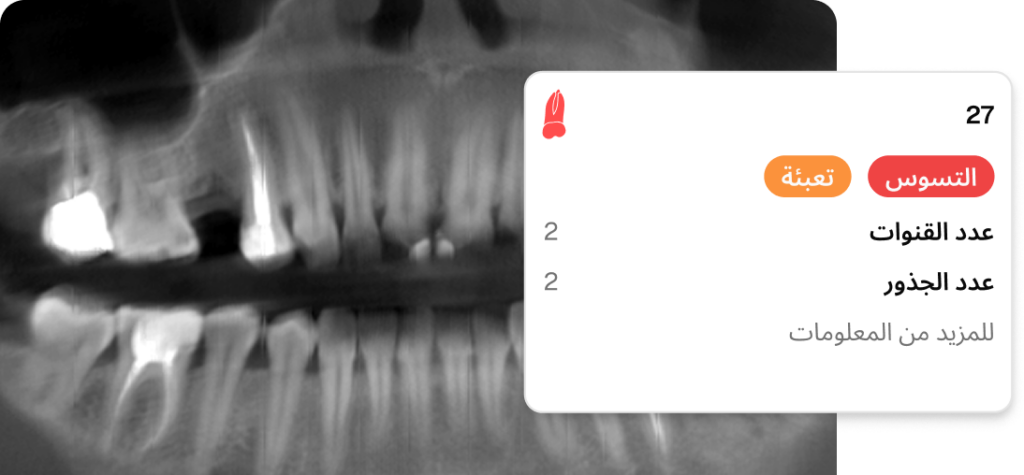

تتيح قدرة برنامج Dentomo على تحديد أكثر من 10 أمراض فموية وأكثر من 14 علاجًا تلقائيًا، مع ميزة البحث الدقيق حسب الكيان أو العيادة أو المستخدم، رؤية شاملة لصحة فم المريض. تمكّن هذه المعلومات القيّمة الأطباء من اتخاذ قرارات مدروسة، مما يؤدي إلى خطط علاجية أكثر تخصيصًا ومستوى رعاية أعلى.

يُسهّل تضمين مكتبة من نماذج الأسنان التفاعلية ثلاثية الأبعاد وشرائح الأسنان المحورية المفصلة في برنامج Dentomo عملية تثقيف المرضى والتواصل معهم. إذ يُمكن لأطباء الأسنان استخدام الوسائل البصرية لشرح التشخيصات وخطط العلاج بشكل أكثر فعالية، مما يؤدي إلى زيادة فهم المرضى ورضاهم.